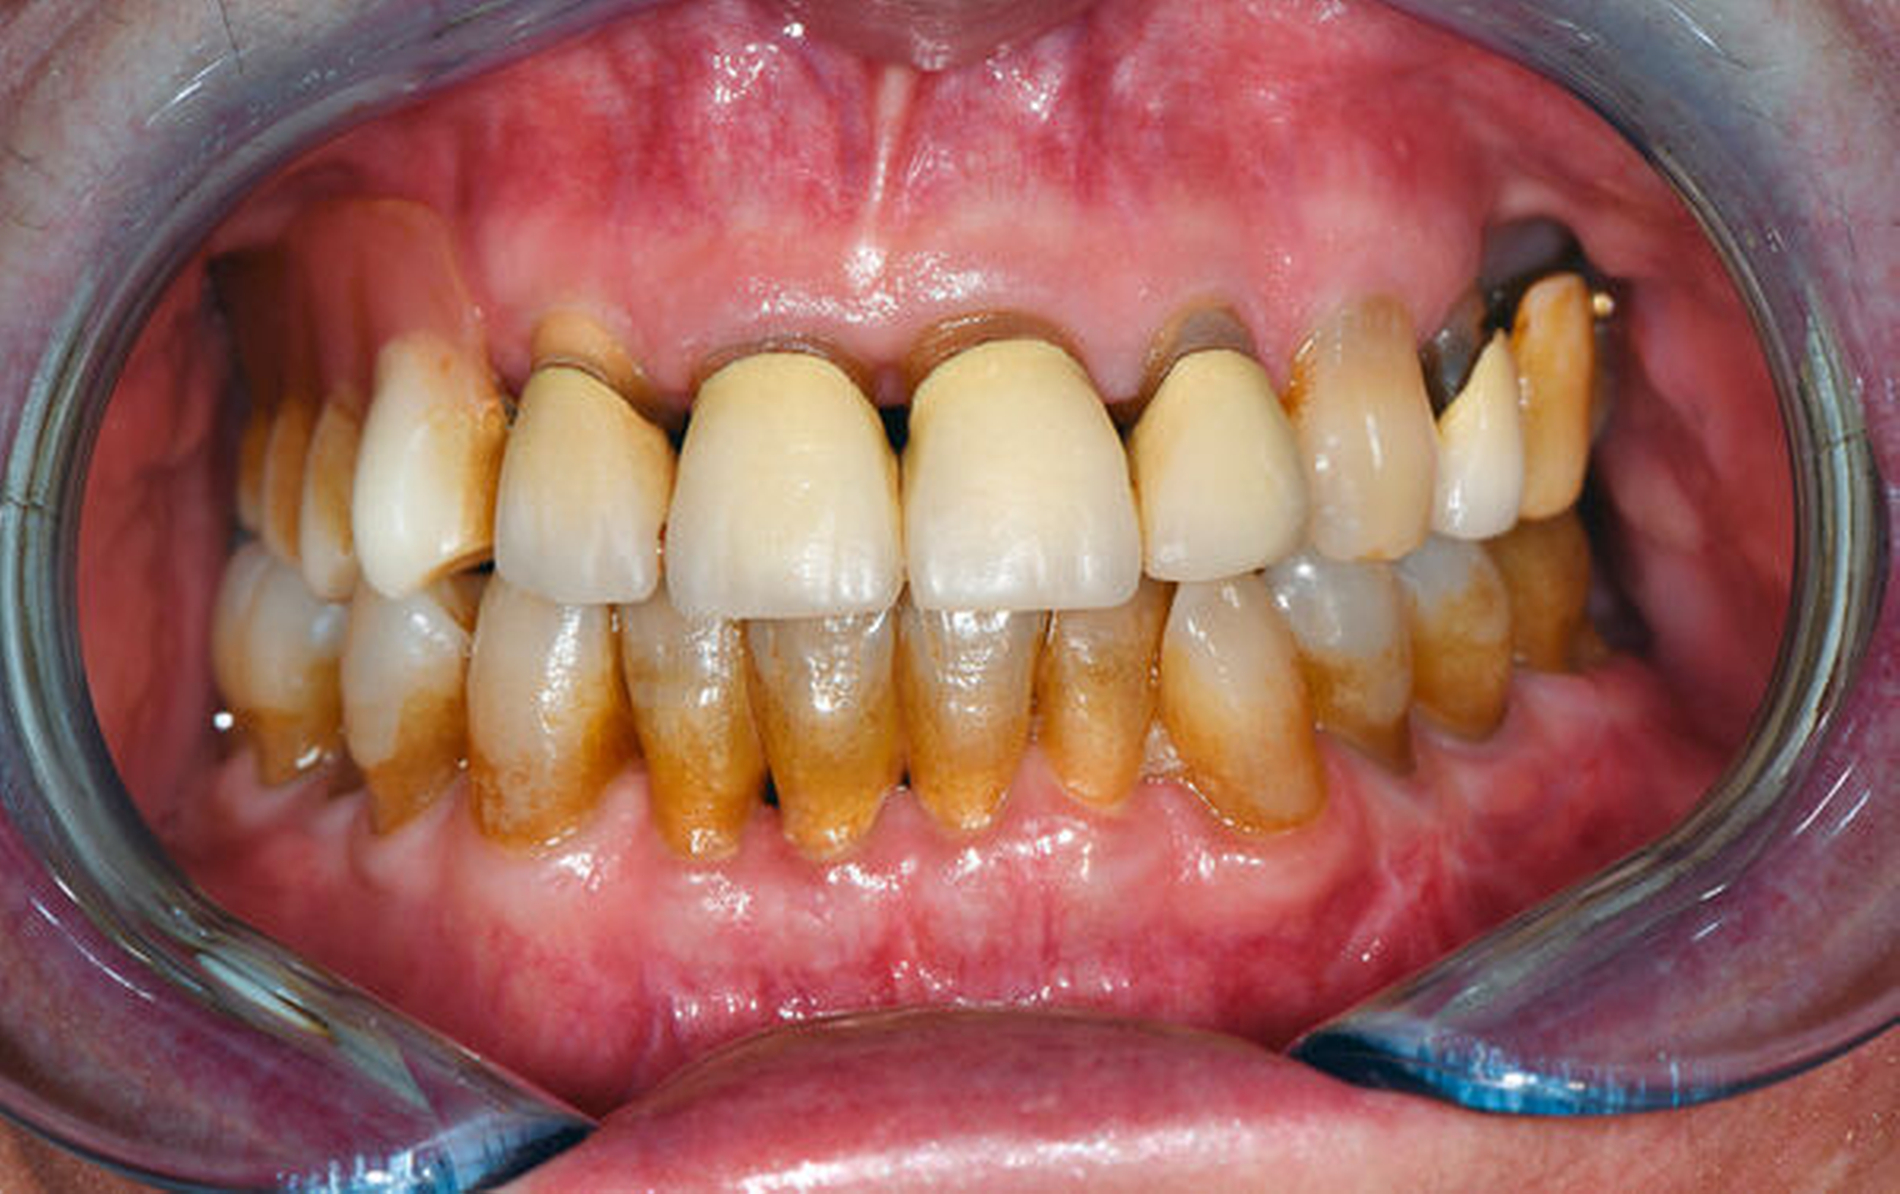

Der postoperative Heilungsverlauf zeigte sich bei kontinuierlich klinisch und laborchemisch rückläufigem Entzündungsgeschehen komplikationslos. Die Schneidekantendistanz betrug postoperativ gemessen 38 mm.

Neben einem engmaschigen Recall wird die Patientin zur Verbesserung der Unterkiefermobilität physiotherapeutisch begleitet. Bezüglich der pulmonalen Hypertonie erfolgt nach konsiliarischer Empfehlung in domo die zeitnahe Weiterbehandlung an einem entsprechenden Zentrum. Aktuell befindet sich die Patientin in einem sehr guten, entzündungs- und schmerzfreien Allgemeinzustand mit einer regelrechten Okklussion und einer guten mandibulären Funktion (Abbildung 5).